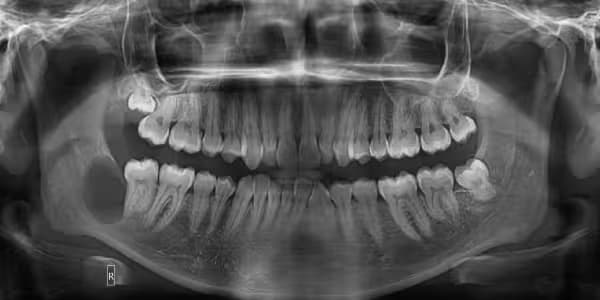

Advanced diagnostic technologies